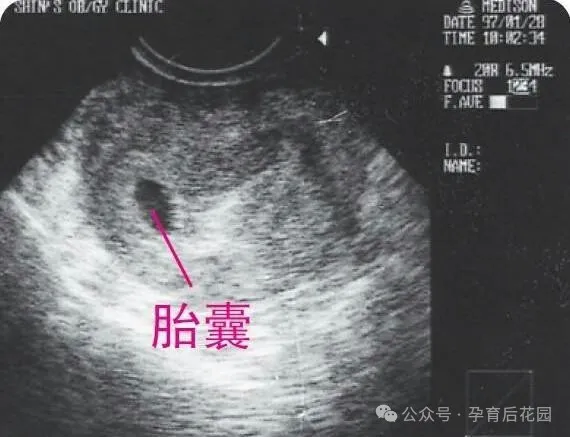

(图:B超显示的早孕宫内妊娠)

HCG 主要由胚胎的滋养细胞产生,在受精第 7 日,血液中就能检测到它的存在,所以通过血液检测能较早发现妊娠。不过,在孕期<5 - 6 周,或者血 β-HCG<1500 - 2000IU/L 时,孕囊还特别小,B 超很难找到。因此,在怀孕极早期,我们主要通过动态监测 β-HCG 水平,来初步评估胚胎发育情况,推测阴道出血的原因。

(1)这是非常关键的一点,通过超声检查,可以清楚看到孕囊是在子宫内,还是在子宫外的其他部位。(2)查看宫内发育的孕囊内是否有卵黄囊、胎芽结构,以及能否探测到胎心搏动,这些都是反映胚胎发育情况的重要指标。(3)观察是否存在胎盘部位蜕膜下积血或血肿,以此初步评估出血原因。有些准妈妈因为过度害怕阴道超声,没能及时进行检查,结果等到宫外孕破裂大出血才紧急就医,差点危及生命,这样的案例并不少见,大家一定要引以为戒。 与腹部超声相比,阴道超声能够更早发现胎盘和胎儿的发育状况,更 准确、及时地判断早孕出血的潜在原因。有些准妈妈因为过度害怕阴道超声,没能及时进行检查,结果等到宫外孕破裂大出血才紧急就医,差点危及生命,这样的案例并不少见,大家一定要引以为戒 当 β-HCG>1500 - 2000IU/L 时,如果阴道 B 超看不到宫内孕 囊,无论有没有出血,都要高度警惕 “宫外孕”。 对于月经周期规律的女性,怀孕 5 周左右,阴道超声就能观察到 宫腔内的孕囊,怀孕 6 周后,大部分准妈妈就能看到宝宝的心跳了。要是迟迟看不到胎心搏动,或者曾经看到过心跳,后来又消失了,那阴道出血很可能是胚胎发出的 “求救信号”,说明它已经停止生长发育了。